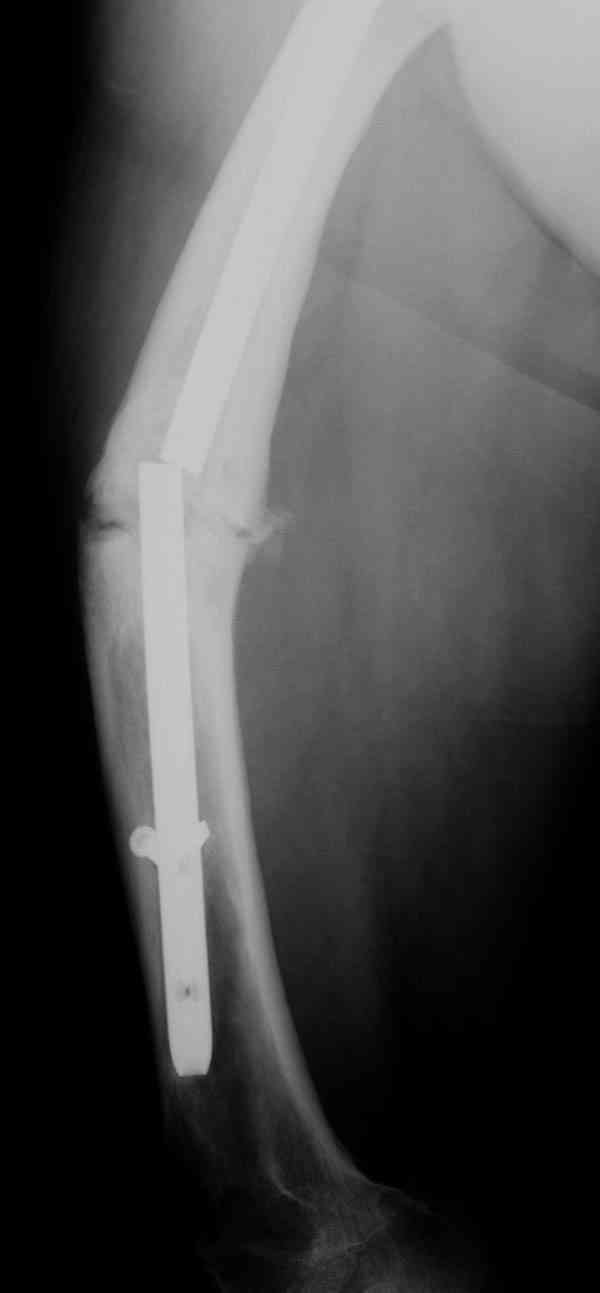

Уважаемые коллеги! У пациента 50-ти лет ложный сустав голени, перелом интрамедуллярного штифта. Перелому около 2 лет, ходить с полной нагрузкой начал через 3 мес. после операции. Боли при ходьбе почувствовал около 2 мес. назад. На данный момент ходит с полной нагрузкой без посторонней опоры. Среди коллег развернулась дискуссия по поводу способа оперативного лечения: -удаление штифта с перештифтовыванием блокированным штифтом с рассверливанием и остеотомией м\б кости -стабилизация зоны ложного сустава по медиальной поверхности LCP-пластиной с декортикацией или без -удаление штифта или без и синтез в АВФ с декотрикацией или без и остеотомией м\б кости

уважаемый коллега! Здесь имеется типичный тугой ложный сустав б/берцовой кости. У нас бы удалили старый стержень, реостеосинтез более толстым стержнем с рассверливанием с блокированием в динамическом варианте. Проблема будет с удалением дистального отломка стержня. Здесь на форуме это вопрос уже рассматривался неоднократно. Поищите по поисковику.Вот здесь, кажется http://weborto.net/forum/1164105478/, http://weborto.net/forum/1192794837

Все перечисленные варианты способны привести к желаемому результату. Несращение здесь - результат нестабильности, так что любой вариант

стабилизации решит проблему. Одного безоговорочно лучшего нет, у всех есть плюсы-минусы.

Наименьший по инвазивности - наложение спицевого аппарата без удаления стержня, с последующей либо дистракцией либо компрессией. Можно и устранить антекурвацию, это тоже создаст стабилизирующее напряжение тканей.

Наиболее быстро достичь опорности без боли и внешних приспособлений - удаление и блокируемый реостеосинтез с рассверливанием. Лучше бы тоже с

восстановлением оси (отклоняющая спица в дистальном отломке, чтобы новый стержень прошел не в старый канал, а кзади от него), еще и для создания дополнительного напряжения тканей в области несращения. Открывать зону несращения не надо.

Сросшаяся малоберцовая как распорка привела к образованию ложного сустава. В таких случаях удаляем сломанный штифт и проводим стимуляцию ложного сустава рассверливанием. Рассверливание канала создает стимуляцию на месте ложного сустава, и динамический вариант блокировки штифта с большим диаметром создаст стабильность. Ранняя нагрузка после остеотомии малоберцовой приведет к сращению ложного сустава.